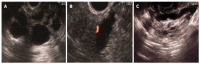

Cystic lesions of the pancreas are being diagnosed with increasing frequency, covering a vast spectrum from benign to malignant and invasive lesions. Numerous investigations can be done to discriminate between benign and non-evolutive lesions from those that require surgery. At the moment, there is no single test that will allow a correct diagnosis in all cases. Endoscopic ultrasound (EUS) morphology, cyst fluid analysis and cytohistology with EUS-guided fine needle aspiration can aid in this difficult diagnosis.